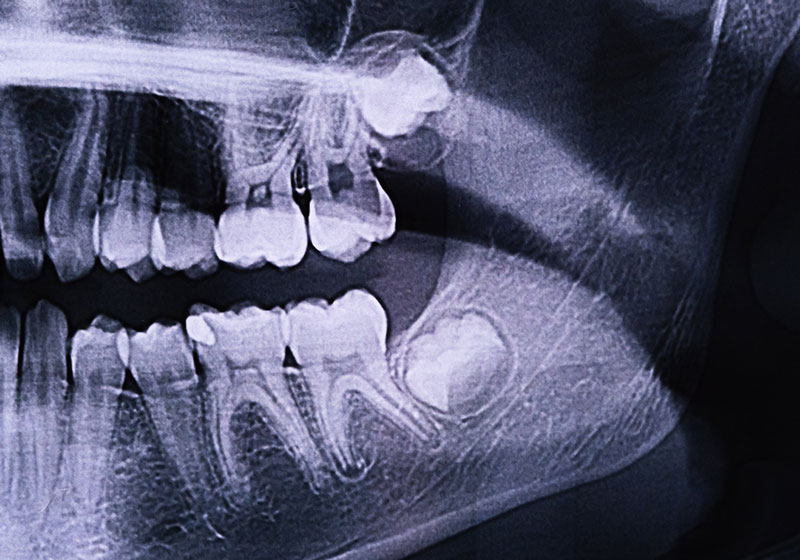

Undergoing wisdom teeth extraction near American Fork, UT, can prevent a world of dental issues. Impacted wisdom teeth can cause misalignment, damage to other teeth, and even lead to painful infections. By removing them, you’re protecting your oral health and saving yourself potential stress and expense down the road.